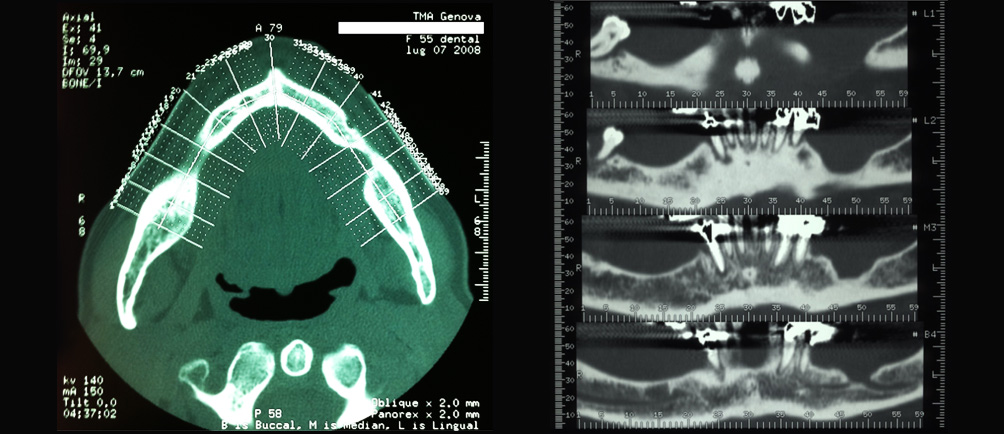

Rigenerazione ossea del pavimento del seno mascellare con incremento verticale di 12 mm ed orizzontale di 10 mm

Risultati estetici e funzionali conseguiti con la CHIRURGIA RIGENERATIVA